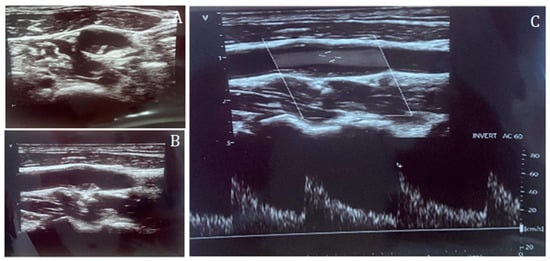

Inclusion criteria were (1) age ≥ 18 years, (2) availability of complete CCTA datasets, (3) availability of a CDUS performed prior to CCTA, and (4) availability of clinical data including age, body mass index (BMI), sex, hypertension, diabetes, smoking status, hypercholesterolemia, and family history of CV disease. Patients with history of CAD, known cardiomyopathy, angina or angina-equivalent symptoms, and chest pain were excluded. CAC score, CAD-RADS classification, and plaque morphology were recorded from CCTA reports. Carotid disease was assessed by CDUS and categorized according to the degree of stenosis: CDUS 0 (no detectable plaque), CDUS 1–49% (mild stenosis), and CDUS ≥ 50% (significant stenosis) (Figure 1 and Figure 2).

Figure 1.

Carotid duplex ultrasound representation of a non-significant lesion of the internal carotid artery in short-axis (A) and long-axis (B), and Doppler assessment (C), confirming the absence of flow acceleration across the plaque.

Figure 2.

Carotid duplex ultrasound representation of a significant lesion of the internal carotid artery in long-axis (A) and Doppler assessment (B), confirming the effective flow acceleration across the plaque.